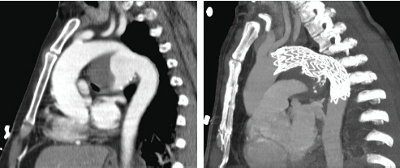

Aussackung der Hauptschlagader im Brustkorb (links), welche durch den Interventionellen Radiologen und in Zusammenarbeit mit den Kollegen der Gefässchirurgie von innen abgedichtet (rechts) werden konnte.